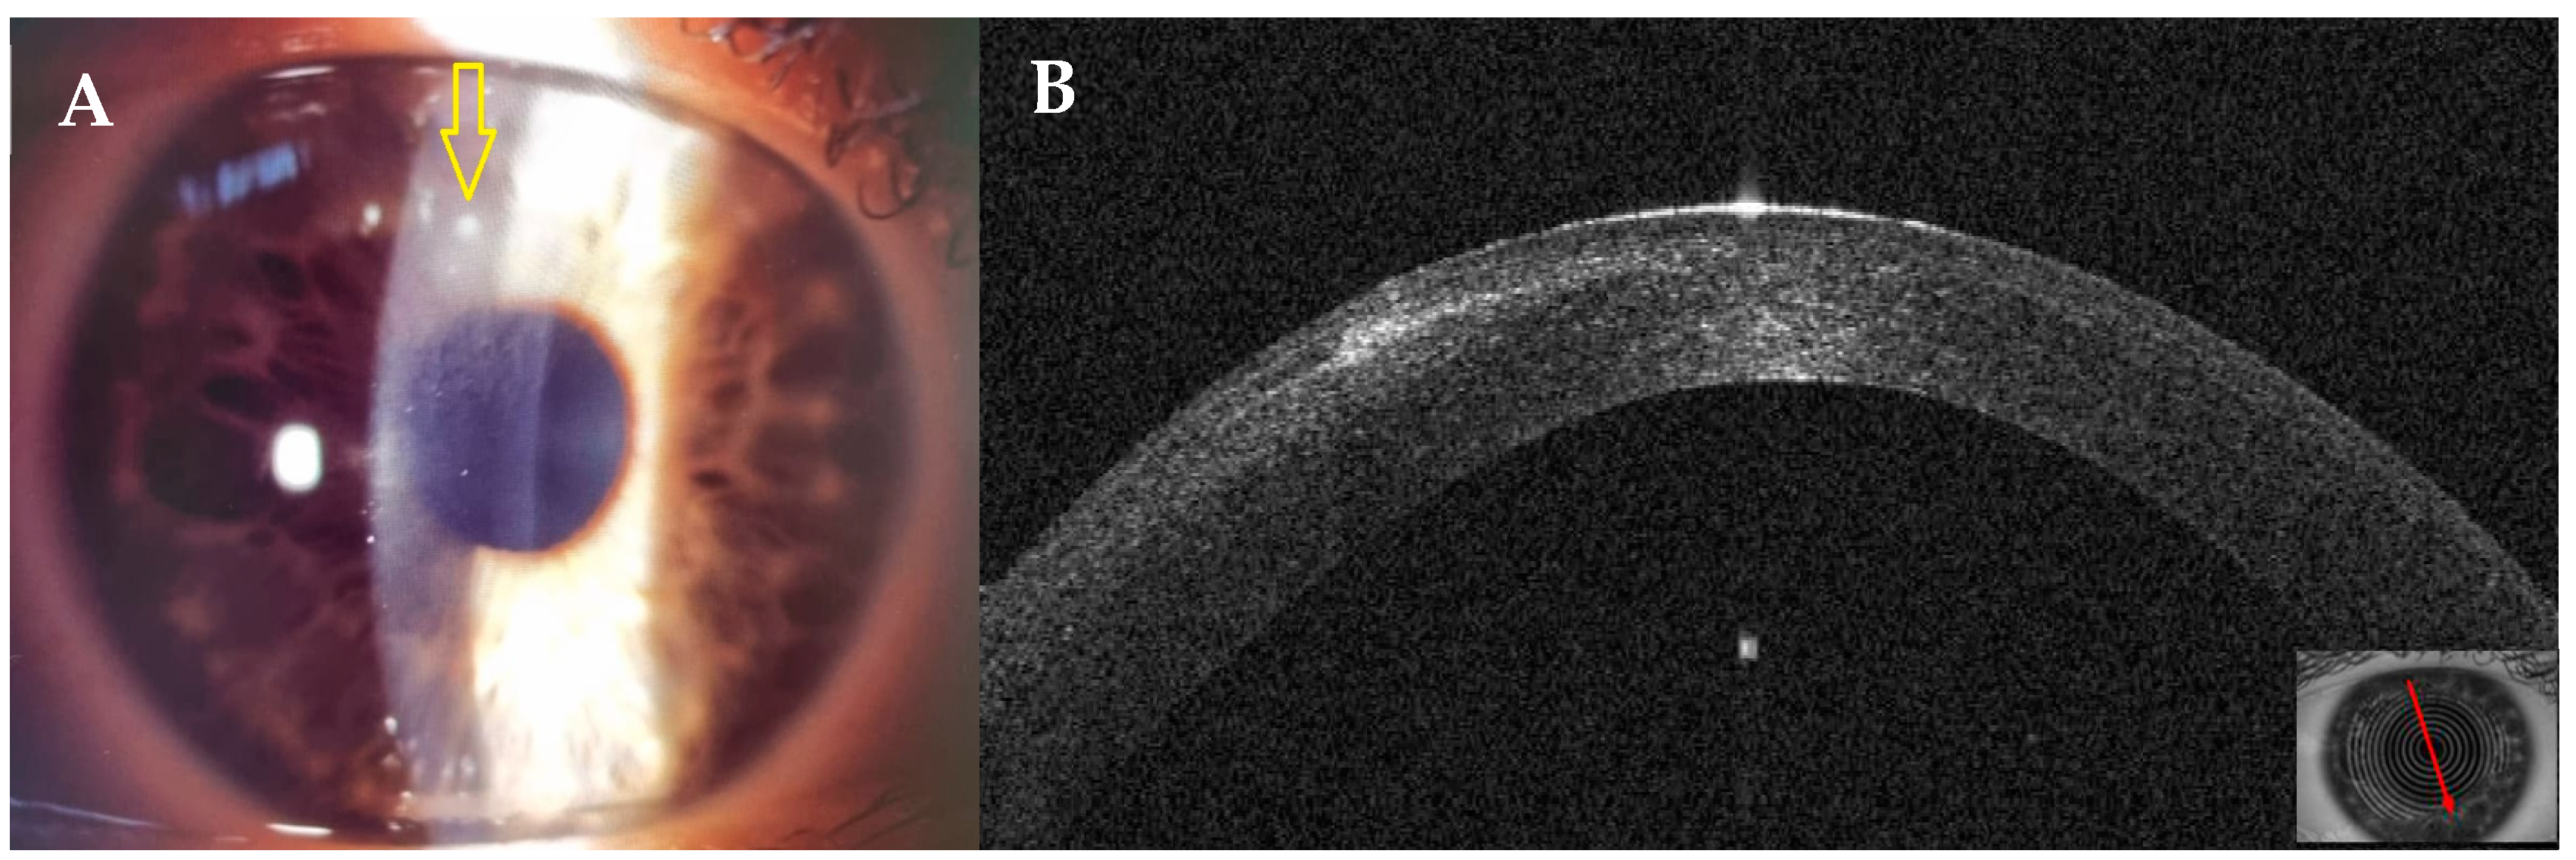

3.4. Patient #4